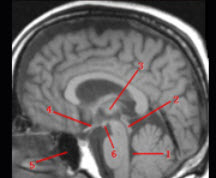

图为大脑正中失状层面,分别标出如图所示1_______________2_______________3_____________4___________5___________6___________________部位。